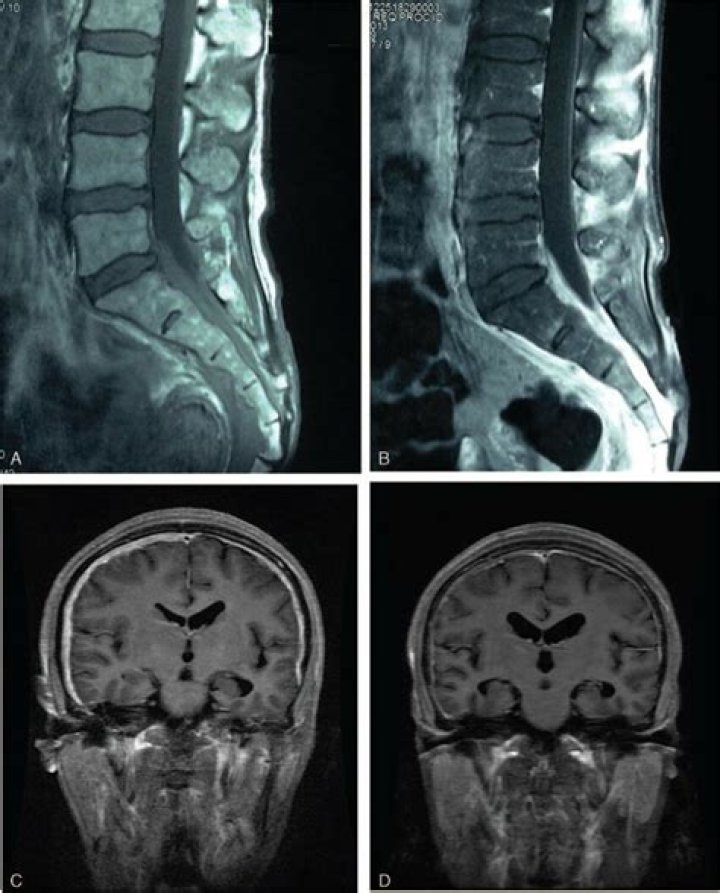

Localized or diffuse thickening of the dura mater may be seen in hypertrophic pachymeningitis that may be associated with rheumatoid arthritis, syphilis, Wegener’s granulomatosis, tuberculosis, and cancer [22–26].

Hypertrophic pachymeningitis is a rare form of diffuse inflammatory disease that causes thickening of the dura mater. It can involve the cranial or the spinal dura or both.

Idiopathic hypertrophic pachymeningitis (IHP) is a rare disease caused by thickening of either the intracranial or spinal dura mater, or rarely both simultaneously. Chronic headache, multiple cranial nerve (CN) palsies, and cervicodynia are the most common clinical manifestations.

Abstract. Pachymeningeal enhancement, synonymous with dural enhancement, is a radiological feature best appreciated on a contrast-enhanced magnetic resonance imaging (MRI). The vasculature of the dura mater is permeable, facilitating avid uptake of contrast agent and subsequent enhancement.